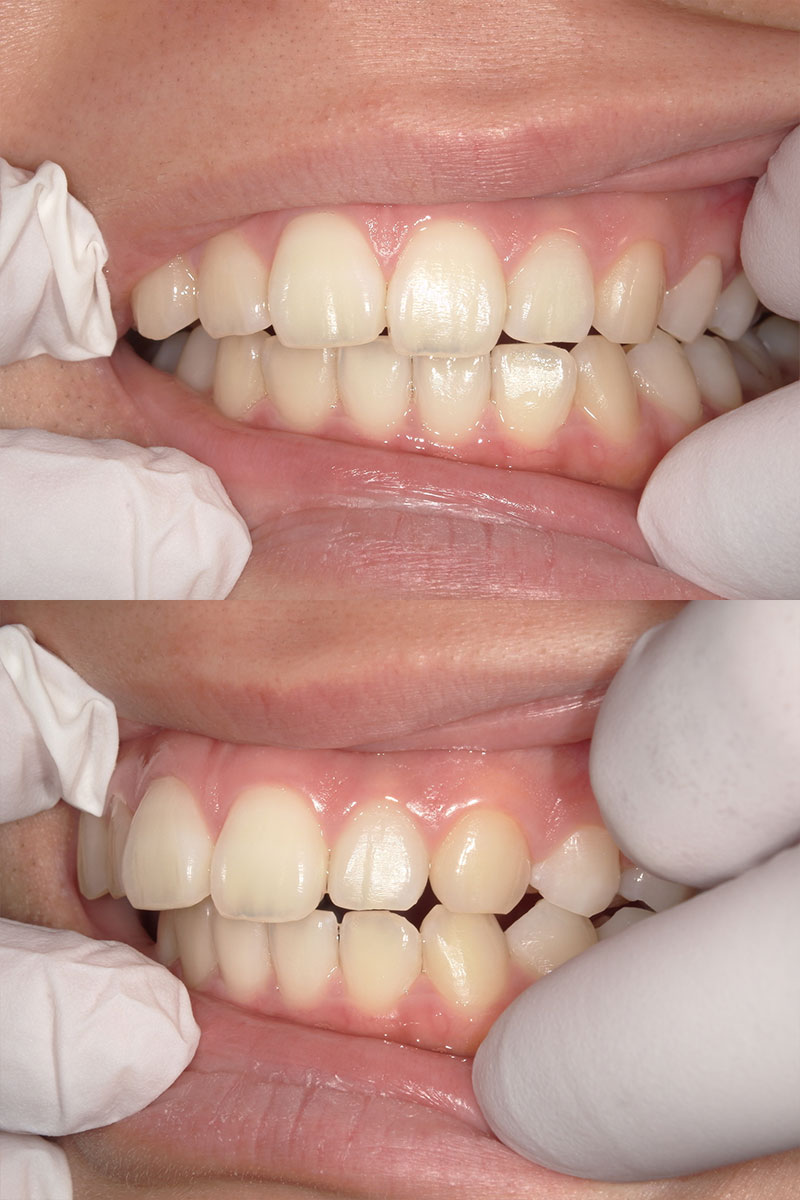

マウスピース矯正

治療前

Before

治療後

After

年齢 19

性別 女性

主訴 歯並びを治したい